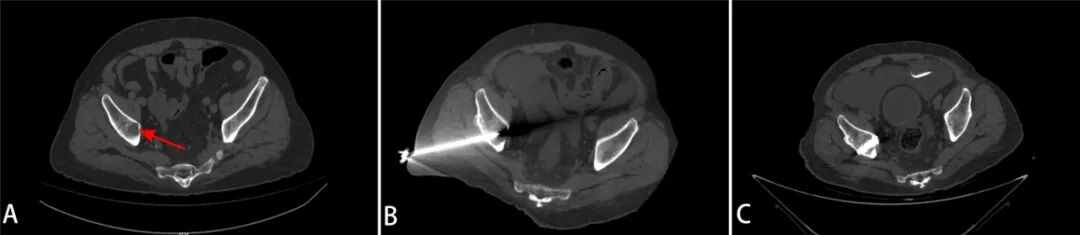

術前髖臼破壞(A),消融針經通道置入病灶(B),骨水泥注入骨質缺損處(C)

第一步:腫瘤消融。在CT引導下,微創介入科主任胡鴻濤通過一根細長的消融針,精準置入病灶中心,利用熱消融技術滅活“燙死”腫瘤細胞,從根源上處理局部病變。

第二步:骨水泥成形。消融后,骨與軟組織科馮和林主任利用同一穿刺路徑向被破壞的骨空腔內注入醫用骨水泥。骨水泥迅速凝固后,像混凝土一樣強化骨骼結構,恢復髖臼的承重功能。